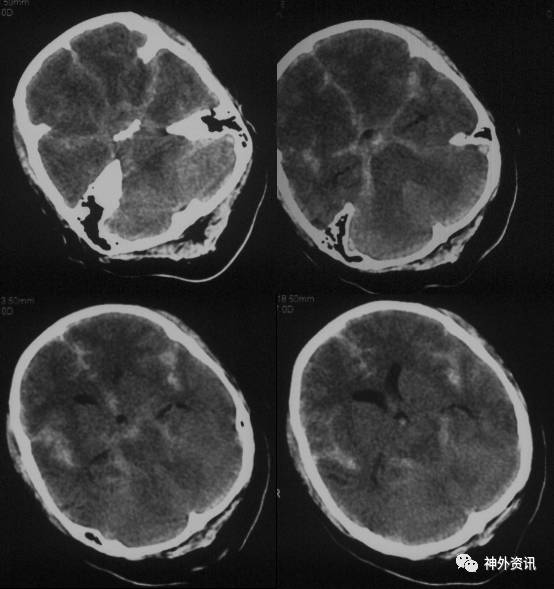

简要病史:4日前与安静状态下突发剧烈头痛伴恶心呕吐,后出现双侧肢体抽搐,持续约2分钟后意识丧失,呼叫不应。就诊于当地医院,CT提示“基底池、环池、四叠体池、双侧裂、大脑镰旁广泛蛛网膜下腔出血”。现就诊于我院,复查颅内CT出血较前减少,DSA提示“左侧颈内动脉眼端、交通段、左侧大脑前动脉A1段多发动脉瘤”。

出血当日CT(2017-03-20): 基底池、环池、四叠体池、双侧裂、大脑镰旁广泛蛛网膜下腔出血。